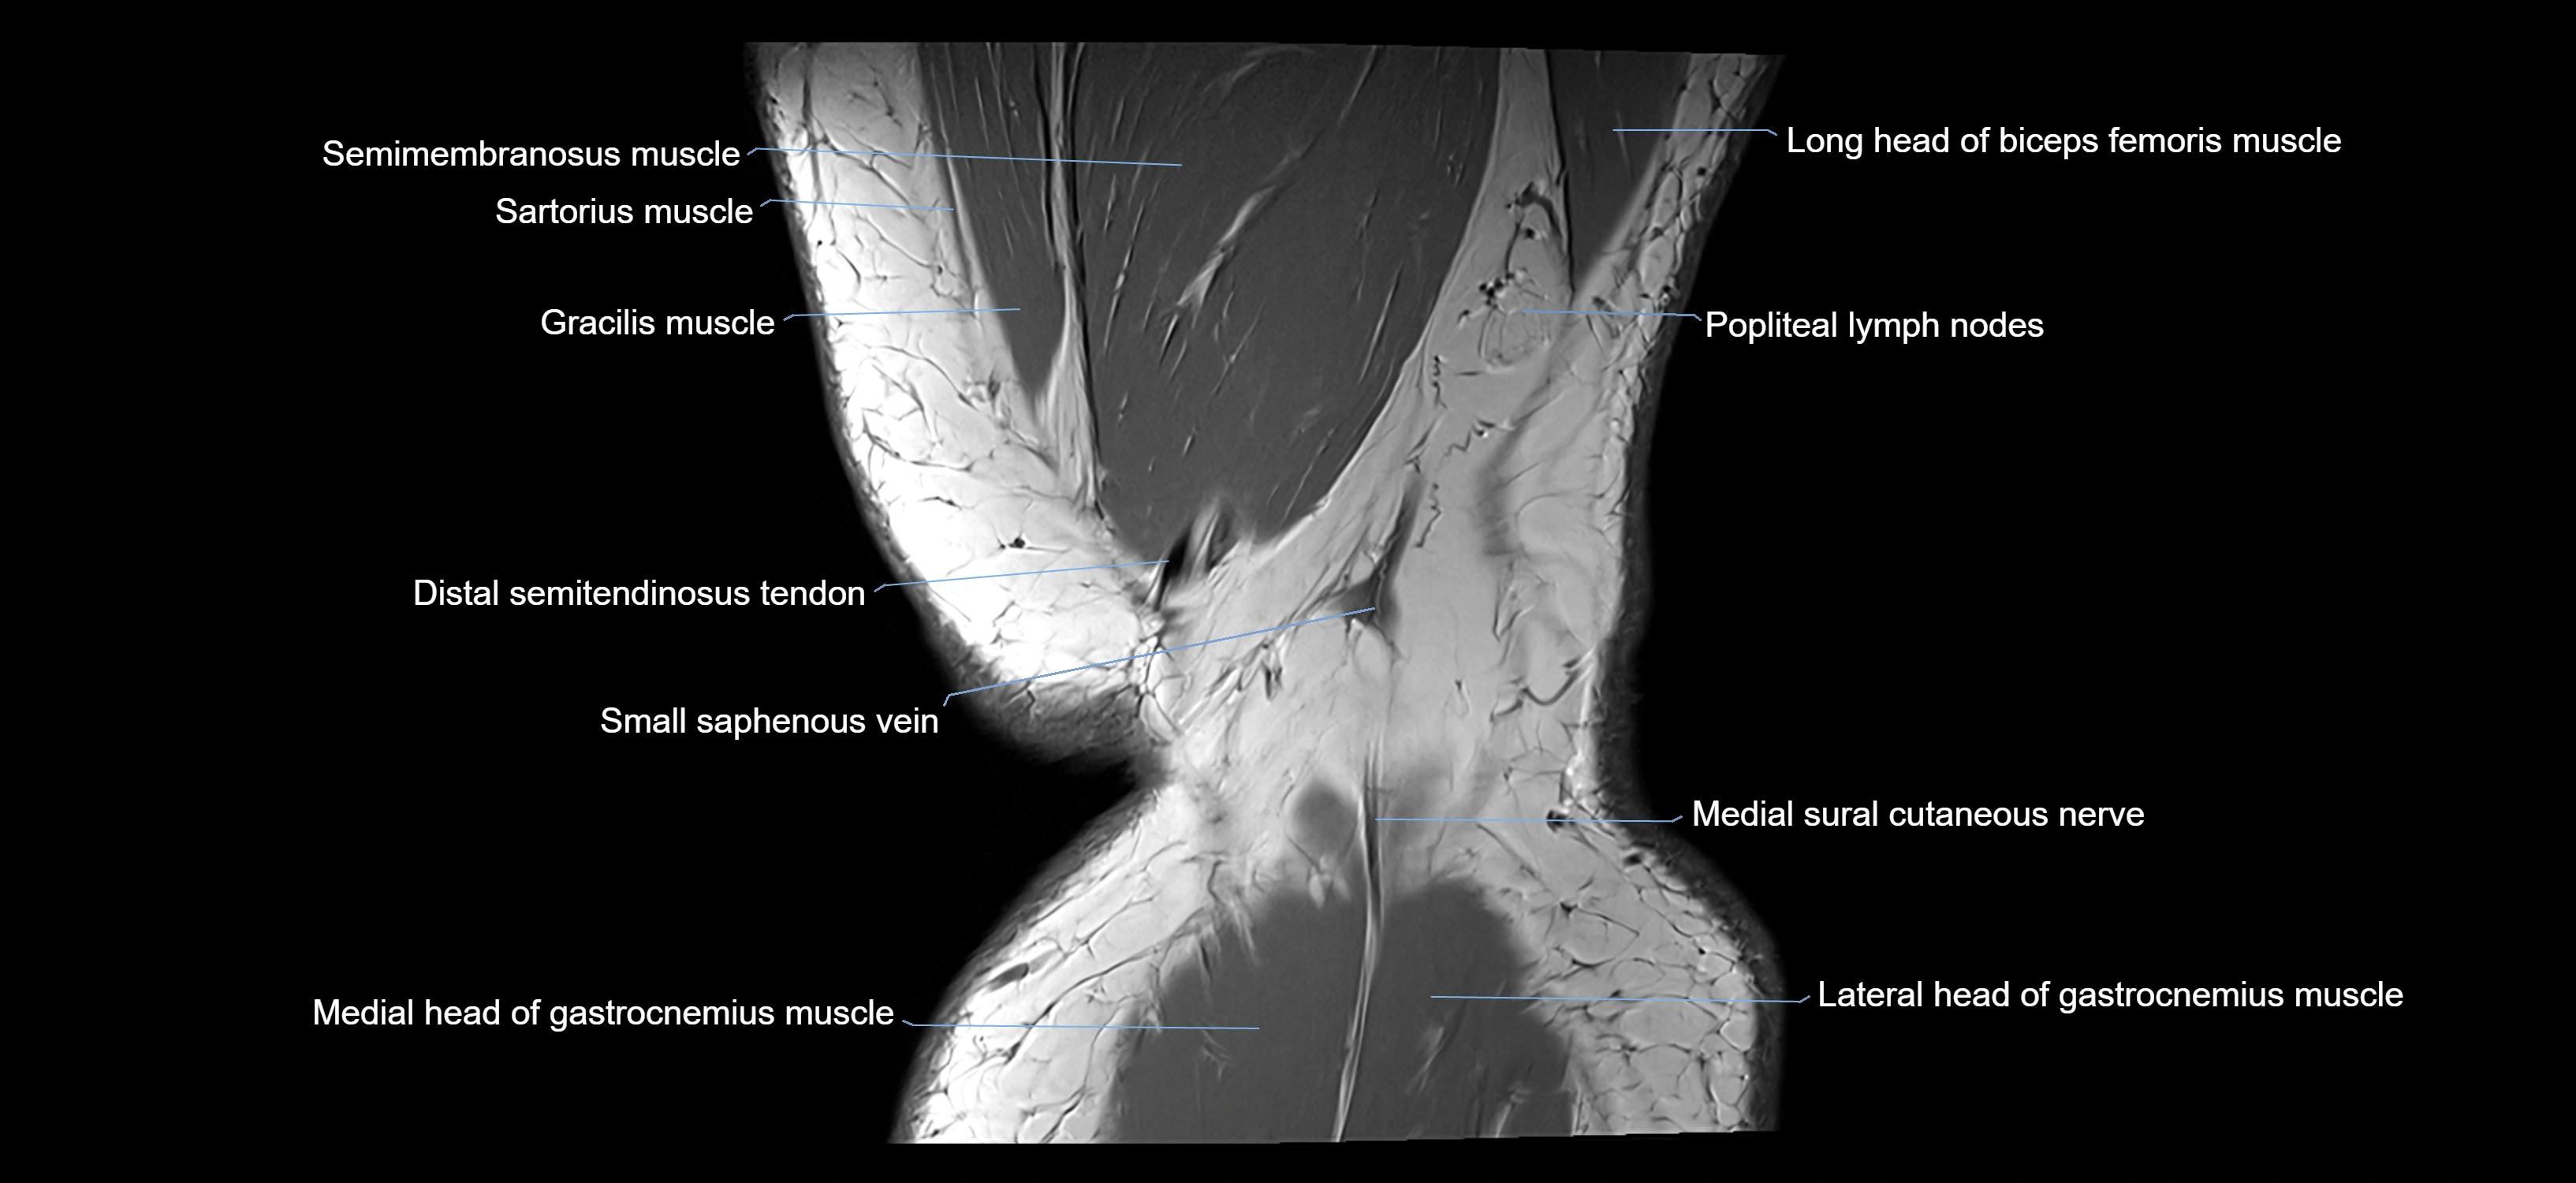

- Biceps femoris muscle (Long head)

- Distal semitendinosus tendon

- Medial head of gastrocnemius muscle

- Lateral head of gastrocnemius muscle

- Medial sural cutaneous nerve

- Popliteal lymph nodes

- Sartorius muscle

- Semimembranosus muscle

- Small saphenous vein